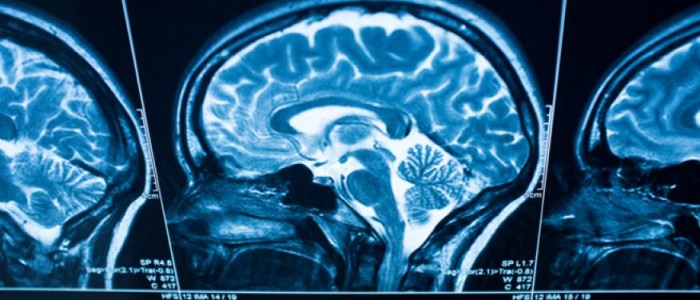

Brain scans could predict patients at risk of major depression

By Kate Kelland LONDON (Reuters) – Scientists studying people with depression say brain scans could be used to predict who is most likely to relapse, an approach that could help doctors make better decisions about who should stay on antidepressants and who should stop. In a small study of 64 patients, the researchers found that significant differences showed up in brain scans of those who later went on to have a recurrence of their depression. While the results need first to be replicated and improved upon, Roland Zahn, who led the work, said the approach may prove important in the future “as there are currently no accurate ways to predict those who will have a recurrence following recovery”.